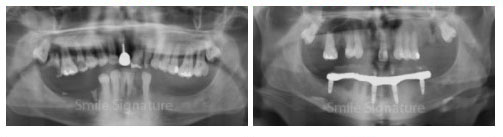

All-on-4 vs All-on-6

The number of dental implants recommended for your full-arch restoration is not a one-size-fits-all solution. It is determined based on your unique bone density and biting force load. Generally, the upper jaw requires a higher number of implants, typically 5 to 6 posts because the maxillary bone is naturally less dense. In contrast, 4 implants are usually sufficient to securely support a fixed hybrid denture.

To determine the precise configuration for your smile, your dentist uses 3D CT scans and X-rays to map bone structure and recommend the specific implant-supported system that ensures long-term stability and comfort.

Upper Jaw

All-on-6 on Upper Jaw

Lower Jaw

All-on-4 on Lower Jaw